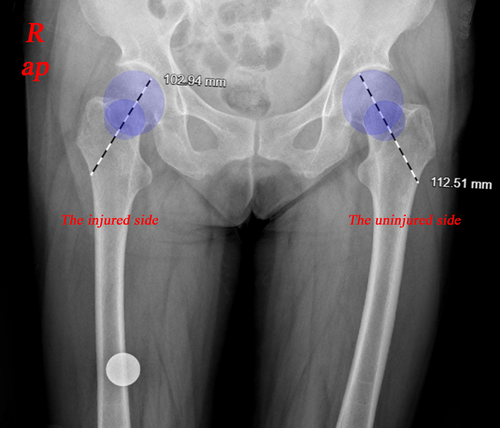

在这项回顾性研究中,2017年5月至2020年7月期间,在中国的一家三级医疗中心,接受“内-外-内”经皮复位技术和内固定手术的外展嵌插型股骨颈骨折患者被纳入经皮复位组。本研究已获得宁波第六医院医学伦理委员会批准(X2022059),所有患者在参与研究前均签署了知情同意书。术前,每位患者均通过标准放射学检查和重建CT进行了常规检查。最终,共有24名患者(7名男性,17名女性)在经皮复位组完成了研究并被纳入最终结果分析。此外,另有24例外展嵌插型股骨颈骨折患者接受了原位固定手术,作为对照组用于功能比较。所有手术均由一名拥有超过15年股骨颈骨折手术经验的外科医生完成,手术植入物由单一设备制造商提供(AO/Synthes Group Co., Ltd., USA)。术后评估由两名外科医生完成。

在术后随访中,所有患者均在24小时内通过X光和CT扫描进行评估。两名外科医生在术后24小时、6个月及2年内评估股骨颈骨折的复位质量,包括颈干角、后倾角以及股骨颈缩短量。出院后,要求患者定期前往门诊进行影像检查和功能评估(Harris髋关节评分,HHS)。此外,通过X光片和症状识别并发症,如固定失败、不愈合及股骨头坏死,直至最终随访。

在经皮复位组中,测量并分析了股骨颈骨折复位质量的放射学参数。术前病例和术后即刻病例的椎弓根角、后倾角和FNS数量存在显著差异(p<0.05)。然而,不同时间点(术后24小时、6个月和2年内)的术后病例测量值没有统计学差异(p>0.05)。